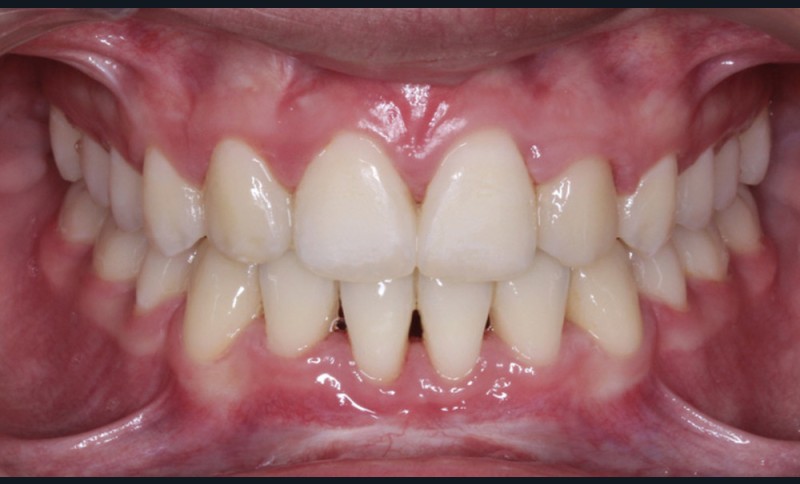

Les caches esthétiques ont été progressivement diminués jusqu’à leur suppression complète. Une fois l’alignement des canines obtenu, la prise en charge de 11 et 21 sur un NiTi .014 a débuté. Des forces très douces avec un contrôle radiologique tous les trois mois ont ensuite permis l’alignement et la fermeture des derniers espaces maxillaires. Une coronoplastie soustractive de 13 et 23 a été réalisée pour les transformer en 12 et 22. La vitalité de 11 et 21 a été conservée. En contention, deux fils collés ont été mis en place (13-23 et 33-43) ainsi qu’une gouttière thermoformée maxillaire amovible à port nocturne. Le traitement a duré vingt-neuf mois (fig. 5a-f).

Le traitement a permis d’améliorer l’environnement parodontal et de mettre en place les canines incluses tout en préservant au maximum les incisives centrales déjà résorbées et en assurant un résultat esthétique pour la patiente.